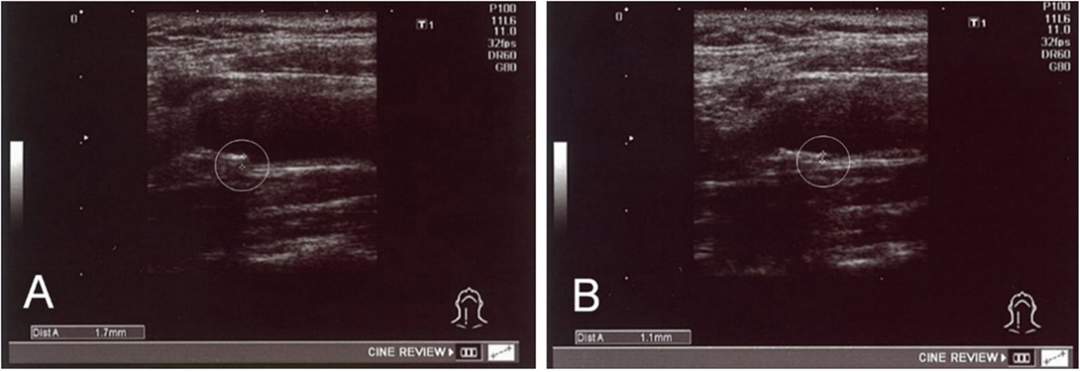

18 例治疗前 IMT 值异常的患者, 治疗后 IMT 值显着下降(p < 0.01)。其中,一名 56 岁男性患者在 Ad-MSC 治疗前 ( a ) 和治疗后 ( b ) 的颈总动脉 IMT 示例显示,治疗后近 4 个月,IMT 从 1.7 毫米下降至 1.1 毫米。